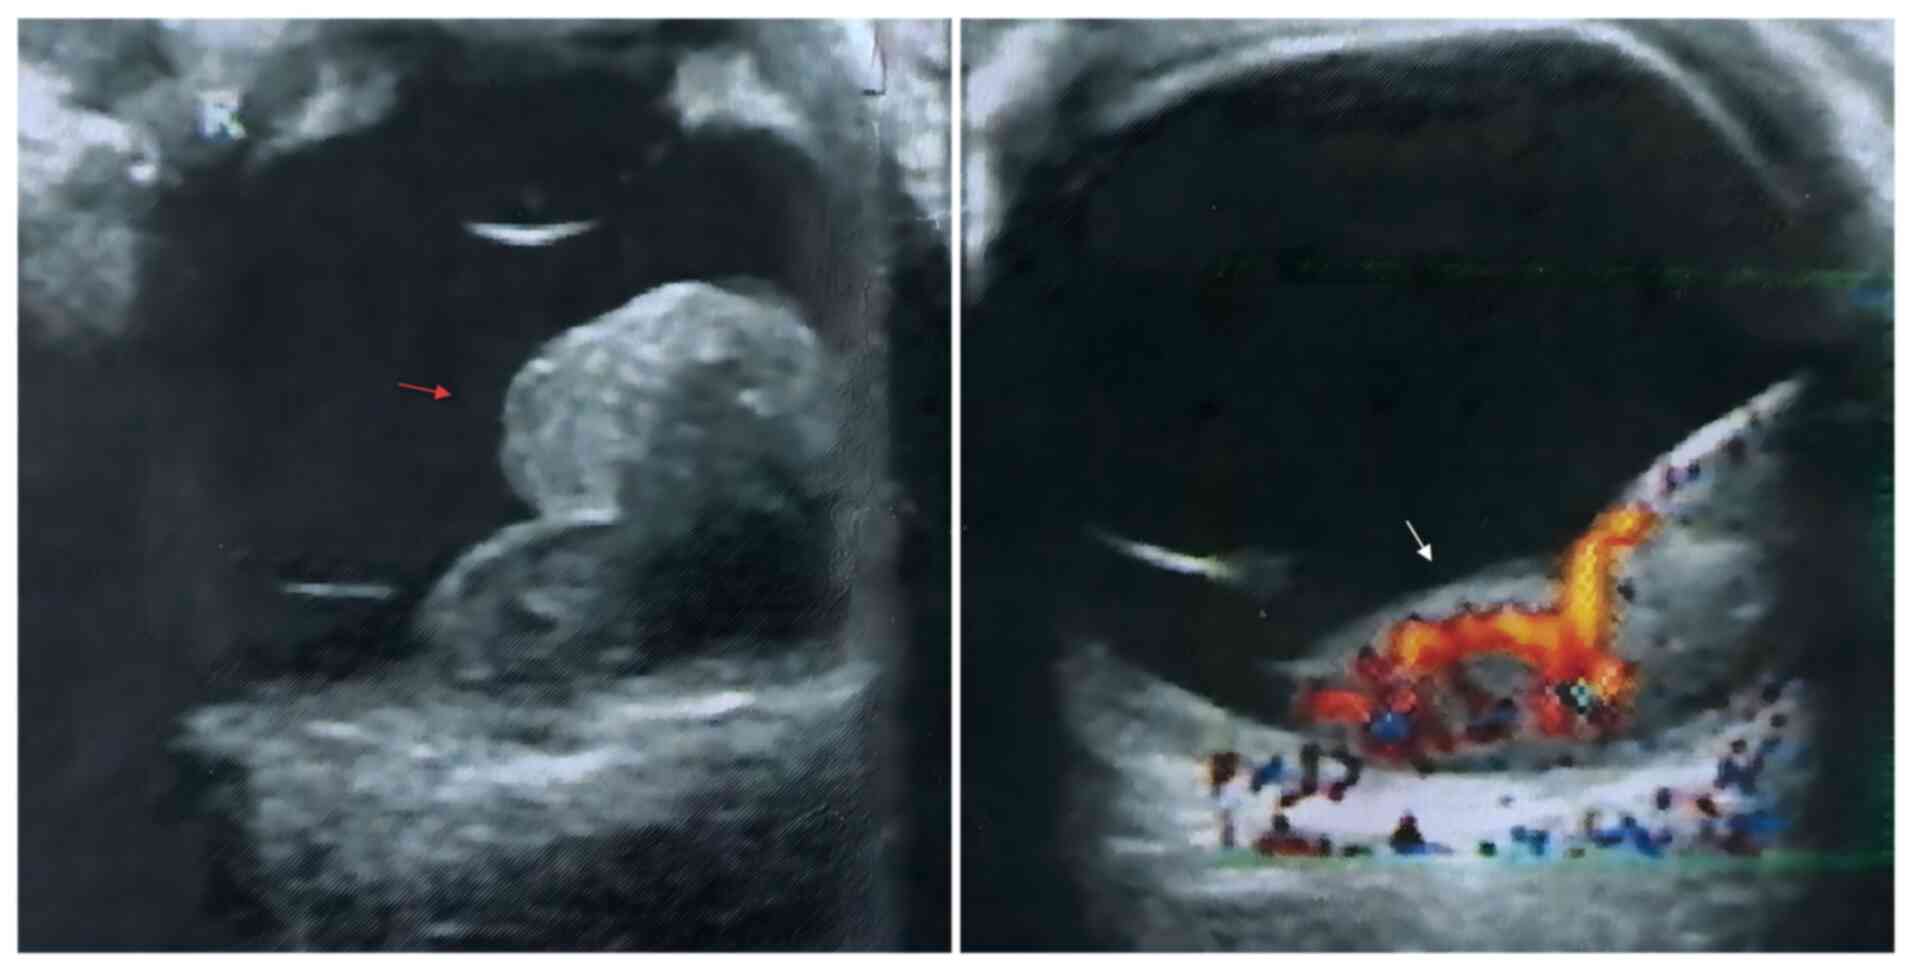

Figure 2

Ocular ultrasound at initial

consultation shows ciliary body leakage and a low-to-medium

echogenic solid mass on the fundus wall (red arrow), with irregular

internal echoes and well-defined margins. A membranous bulge with

abundant internal blood flow is observed (white arrow).